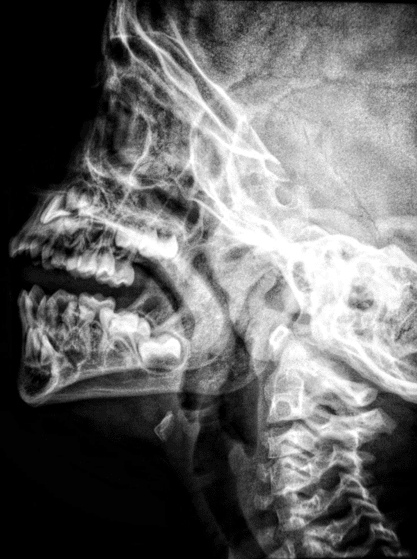

Several imaging modalities have experienced significant improvements through technological innovation. MRI, CT, ultrasound, and X-ray systems now deliver sharper images with lower radiation exposure and faster processing times. For example, modern CT scanners can capture detailed cross-sectional images of the body within seconds, reducing the discomfort of long scan times for patients.

MRI technology has evolved to produce clearer images of soft tissues, allowing specialists to diagnose neurological, musculoskeletal, and cardiovascular conditions with greater accuracy. Ultrasound machines now incorporate real-time 3D and 4D imaging, offering dynamic views that support better assessments during pregnancy and cardiac evaluations. Even traditional X-ray systems have benefited from digital enhancements, producing sharper images while reducing the amount of radiation required.